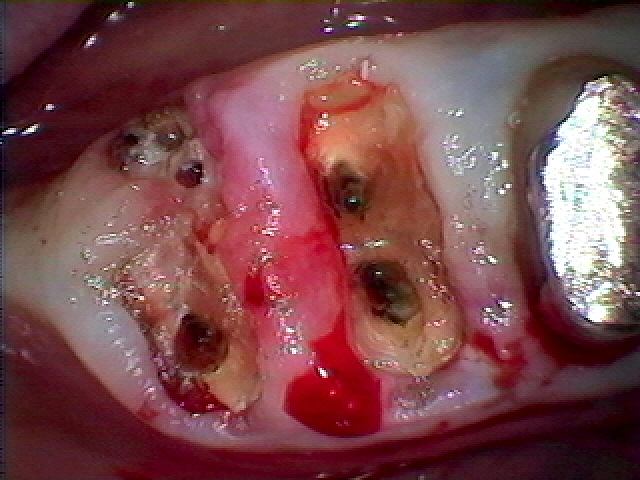

切開して排膿を行っています

近親婚にはヒビが入っており遠心根も分離して厳しい状態でした

よく持ったとも思います